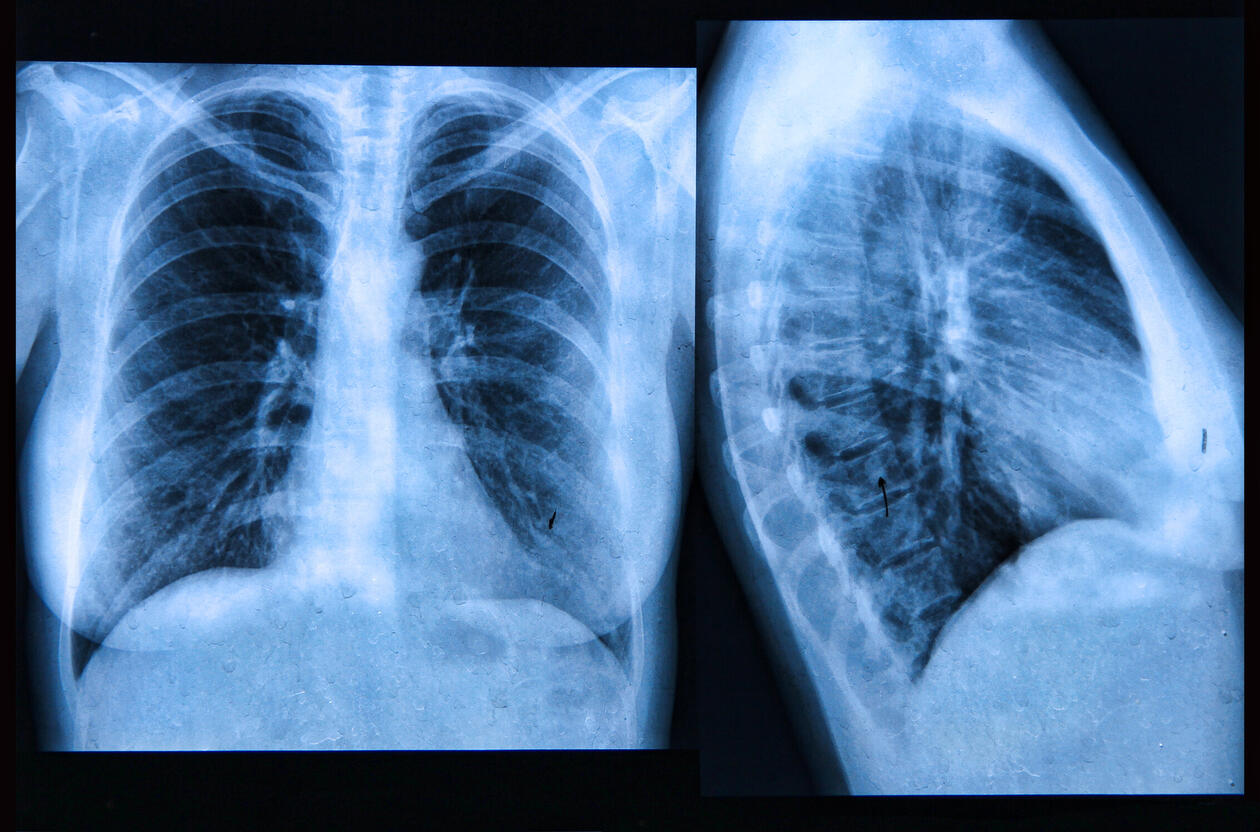

Røntgen av lunger

LUNGEFIBROSE: Personer med lungesykdommen Idiopatisk Pulmonal Fibrose (IPF) har ikke de samme mikroorganismene i luftveiene som friske eller KOLS-pasienter, viser ny forskning.